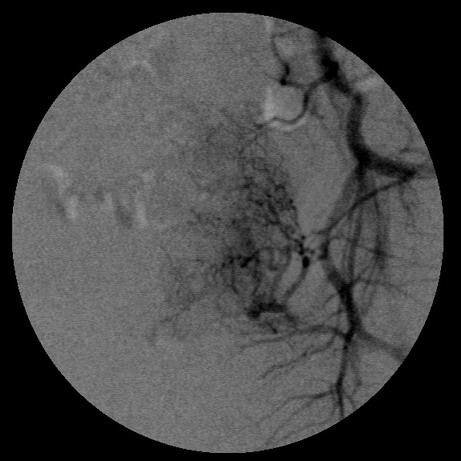

女,35岁,子宫多发肌瘤

子宫动脉增粗,分支数量增多,迂曲,染色明显并排空延迟